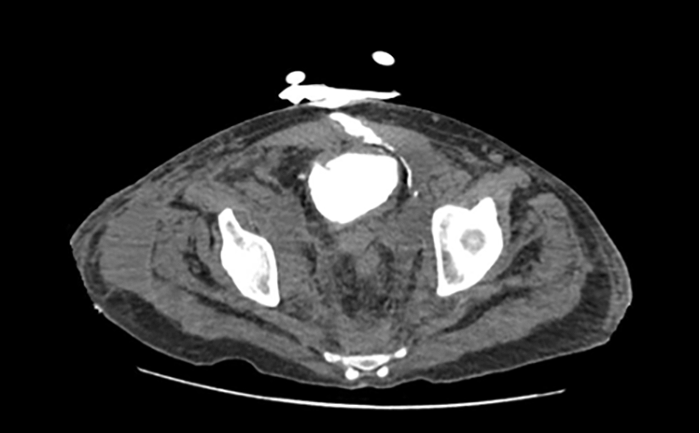

Complications such as visceral necrosis can arise, particularly if nonselective internal iliac AE has been performed.5 There are four previous case reports of bladder necrosis following AE for exsanguinating pelvic injury.6‒9 In all cases, bladder necrosis occurred a few weeks after AE. It may present with hematuria,8 wound infection,9 or, in our case, with a vesico-cutaneous fistula (Figure 2).

Figure 2. CT Cystogram Demonstrating Contrast Extravasation Through Fistula. Published With Permission